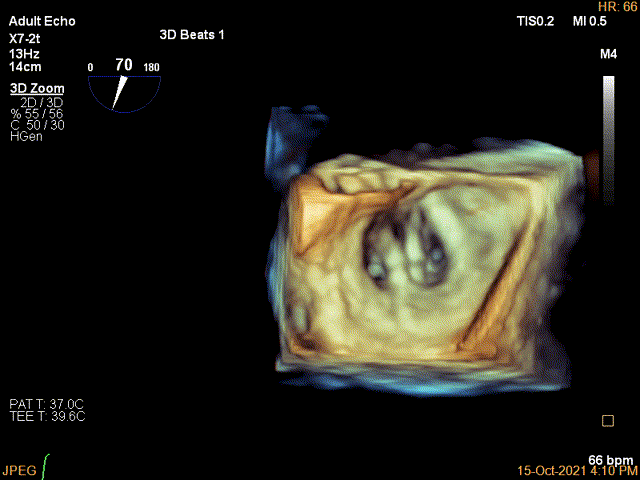

3D-color MV view:极大量返流,1、2区均有受累

3D确认左房较大,穿刺点位近似于3点位

3D视图下大鞘位置及长度测量